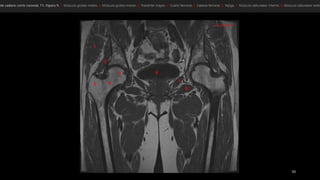

• El músculo glúteo mayor (GMa).

• músculos semimembranoso (sm), semitendinoso (st)

y la cabeza larga del bíceps femoral (elb).

• músculo semimembranoso tiene su propio tendón

(1).

• semitendinoso y la cabeza larga del bíceps se originan

en la cara lateral de la tuberosidad isquiática -en un

tendón común (2).

• nervio ciático (NC). TM, trocánter mayor.

• El músculoglúteo mayor (GMa). • músculos semimembranoso (sm), semitendinoso (st) y la cabeza larga del bíceps femoral (elb). • músculo semimembranoso tiene su propio tendón (1). • semitendinoso y la cabeza larga del bíceps se originan en la cara lateral de la tuberosidad isquiática -en un tendón común (2). • nervio ciático (NC). TM, trocánter mayor.